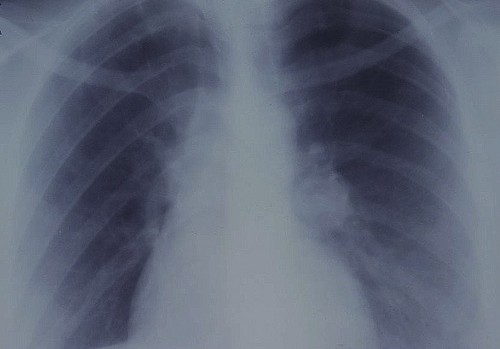

Lung cancer is diagnosed with the help of the tests described below: • Chest X-ray: It is the first test done to diagnose lung cancer. Cancers big enough can be easily visualized on an X-ray as white grey mass. • CT scan: A computerized tomography (CT) scan is usually performed after administering a radioactive dye to the patient. The lungs can be better visualized in this manner. • PET-CT scan: A positron emission tomography CT scan is useful in diagnosing early stage cancers as it can help in locating active cancer cells. • Bronchoscopy: Bronchoscopy is useful in centrally located tumors. It helps in visualizing the tumor and allows specimen to be taken for biopsy. • Sputum examination: Sputum is taken for cytological examination to see the presence of cancer cells. • Percutaneous needle biopsy: Needle is guided to the tumor site through skin with the help of CT scanner and specimen is collected for the purpose of biopsy.